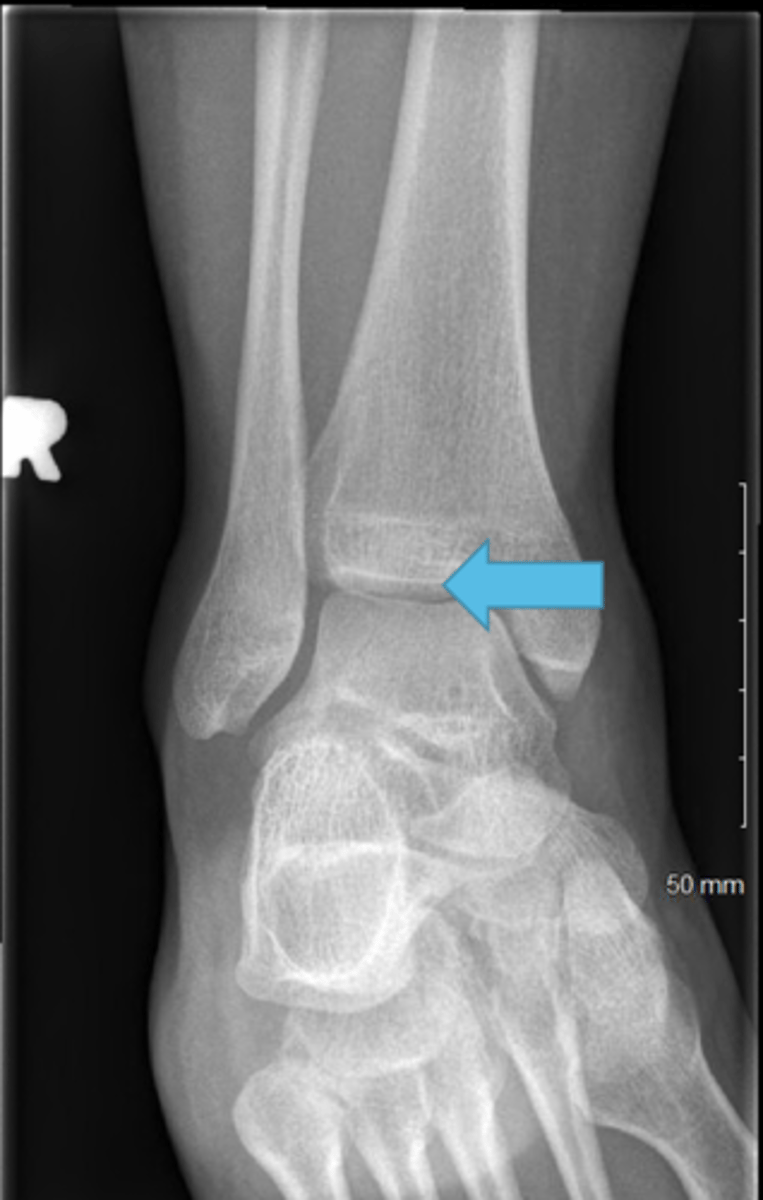

Medial malleolus

Articular facet of medial malleolus

Tibial plafond

Inferior articular surface

Fibular notch

Lateral malleolus

Malleolar fossa

Articular facet of lateral malleolus

malleolar fossa and articular facet of lateral malleolus will face posterior and the malleolus will be lateral